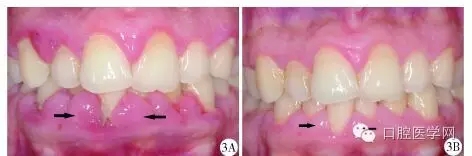

2013年1月,患者因前牙區(qū)牙齦腫脹伴刷牙出血就診于北京協(xié)和醫(yī)院口腔科,行下前牙區(qū)牙齦組織活檢,切片示上皮下炎癥性的纖維組織增生,血涂片檢查未見(jiàn)確切異常,行洗牙治療后自覺(jué)牙齦腫脹緩解不明顯,1個(gè)月后就診于北京大學(xué)口腔醫(yī)院牙周科,口內(nèi)檢查發(fā)現(xiàn)全口牙齦乳頭普遍紅腫增生,質(zhì)地韌,上、下前牙區(qū)尤為明顯(圖3A)。牙周探診深度(probing depth,PD)普遍4~7mm,中等量菌斑,探及大量齦下牙石,探診出血74.0%。全口根尖片顯示普遍的牙槽骨輕度吸收(圖4)。

基礎(chǔ)治療后6周復(fù)查時(shí)患者的牙齦色、形、質(zhì)與口腔衛(wèi)生情況都有了極大改善(圖3B),牙周檢查表顯示治療前后患者每顆牙的平均PD變化(圖6),探診出血也由74.0%下降到33.3%。